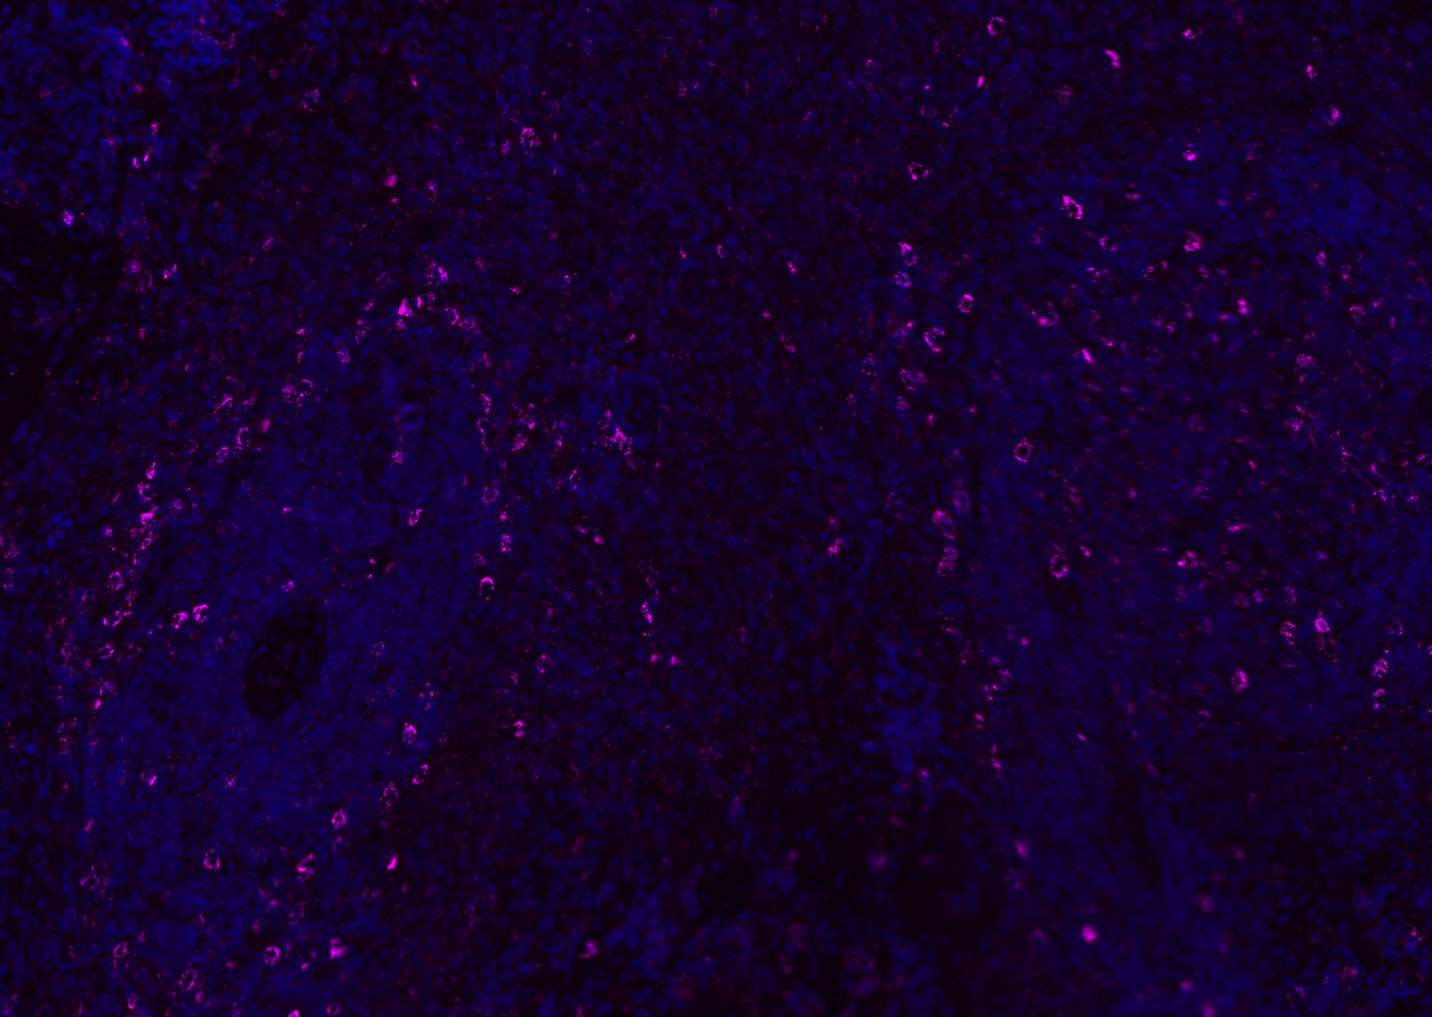

Paraformaldehyde-fixed, paraffin embedded (rat spleen); Antigen retrieval by boiling in sodium citrate buffer (pH6.0) for 15min; Blocking buffer (normal goat serum) at 37°C for 30min; Antibody incubation with (CD8B) Polyclonal Antibody, Unconjugated (bs-4914R) at 1:200 overnight at 4°C, followed by a conjugated Goat Anti-Rabbit IgG antibody (bs-0295G-AF488) for 90 minutes, and DAPI for nuclei staining.